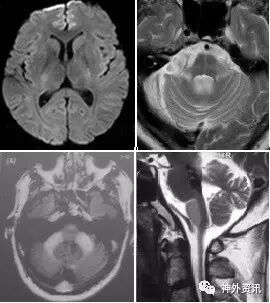

(重要申明:以下每个部分会配磁共振图片,因疾病和影像之间存在同病异象、同像异病,为避免误导,图片不标注疾病,其各自鉴赏,另其中的部分图片来源于网络,有疑问可与本人联系)

各种动脉性、静脉性血管病、静脉窦血栓形成、动脉夹层致脑梗塞、脑小血管病、脑动静脉畸形、CAA等,Moya-Moya也可出现脑实质的多发病灶,易被误诊为脱髓鞘。

除此之外,还有一些解剖结构变异造成的病变,如V-R间隙扩大,灰质异位等。